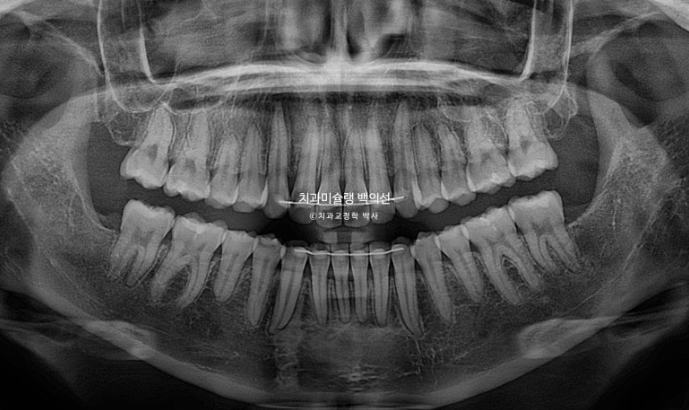

25.09

2년간 치료기간 동안 치근흡수는 없고 치아뿌리 평행도는 좋습니다.

앞니가 뒤로 들어가면서 입을 다무는 것이 편해졌고

큰어금니가 약 2mm 사랑니 공간으로 잘 이동했습니다.